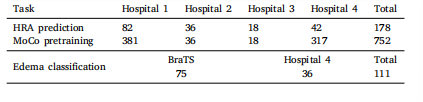

3.1. Material

For HRA prediction, the MRI images of gliomas used in this studywere obtained from Nanfang hospital (Hospital 1, 82 samples), TheFirst Affiliated Hospital of Zhengzhou University (Hospital 2, 36 samples), Sun Yat-sen University Cancer Center (Hospital 3, 18 samples),and Zhujiang hospital (Hospital 4, 42 samples). A total of 178 sampleswith gliomas were collected from these hospitals. Specifically, onlythose who met the following conditions were accepted: (1) gliomaswere diagnosed either clinically or pathologically; (2) samples withsurgical treatment were complete glioma resection, which meant thatno visible glioma remained in the early postoperative (before radiotherapy) MRI images; (3) MRI images were recorded at early post-operationand at the time of recurrence; (4) each sample contained four standardstructural MRI sequences (i.e., T1, T2, T1C, and FLAIR).The operative cavity was delineated by clinical experts on the T1CMRI images during early post-operation. For HRA delineation, theregions of glioma recurrence were initially observed on the T1C MRIimages at the time of recurrence. On the basis of clinical knowledgeand experience, HRA was then mapped back and delineated on T1CMRI images at early postoperation. In addition, a morphology-baseddilation algorithm was used for a uniform 1.5 cm expansion of theoperative cavity, and the expanded margin was used as a possiblerecurrence area. Moreover, the operative cavity combined with the1.5 cm margin was used as the region of interest (ROI). All MRI imageswere preprocessed as follows. First, N4 correction was performed on allMRI images to remove bias field artifacts. Second, all MRI sequences ofa sample were registered to the T1C MRI image. Third, skull strippingwas used to remove the skulls. Fourth, intensity normalization wasimplemented to scale the intensities to [0,1]. Fifth, for each slice ofan image, a minimized rectangle that covered the ROI was used tocrop the corresponding slice image. The cropped result, which wasdefined as rectangular ROI, was resized to 96 × 96, and it was usedas the input of our network. Moreover, given that our method is apatch-based prediction approach, each input was evenly divided into3 × 3 (total of 9) patches, with each patch having a size of 32 × 32(Fig. 3). Specifically, the central patch represented the operative cavity,whereas the eight other patches represented the extended 1.5 cmareas. Therefore, the relationship between the operative cavity andsurrounding areas was explored.We pretrained the encoder using MoCo on 752 samples from fourhospitals (381 from Hospital 1, 36 from Hospital 2, 18 from Hospital 3,and 317 from Hospital 4) under a broad inclusion criterion: (1) gliomaswere diagnosed either clinically or pathologically; (2) samples with surgical treatment can be complete or partial glioma resection; (3) sampleswith incomplete MRI sequence data can be included. All data used totrain MoCo were subjected to the following preprocessing procedures:N4 correction, registration, skull stripping, and intensity normalization.Moreover, all images were randomly cropped and resized to 96 × 96as input for the network to maintain consistency with the downstreamtask.For edema classification, we used data from 75 LGG from the braintumor segmentation (BraTS) dataset and 36 samples with meningiomafrom Hospital 4. The meningioma cases were included in accordancewith broad inclusion criteria: (1) diagnosis was established either clinically or pathologically, and (2) each sample had four standard preoperative structural MRI sequences available. The edema regions in Hospital4 were manually delineated by clinical experts, and those in the BraTSdataset were provided as a part of publicly available annotations.In both cases, the edema regions were used for classification. Then,all data in Hospital 4 were subjected to the following preprocessingprocedures: N4 correction, registration, and skull stripping. Followingpreprocessing, intensity normalization was performed on both Hospital4 and BraTS dataset to map voxel intensities to the [0, 1] range.For each MRI slice, a minimal bounding rectangle encompassing theedema was computed and used to crop the corresponding slice. Thecropped images were then resized to 96 × 96 pixels and served as inputsto our network. Moreover, given that our method was a patch-basedprediction approach, each input was evenly divided into 3 × 3 (total of

patches, with each a patch having a size of 32 × 32.This retrospective study is approved by the Ethics Review Committee of Zhujiang hospital and Sun Yat-sen University Cancer Center.Obtaining written informed consent is waived because of the retrospective design of the study. All samples’ data are anonymized (see Table1).

3.1 材料 本研究中用于高风险复发区域(HRA)预测的胶质瘤MRI图像来自南方医院(医院1,82例样本)、郑州大学第一附属医院(医院2,36例样本)、中山大学肿瘤防治中心(医院3,18例样本)和珠江医院(医院4,42例样本)。共从这些医院收集到178例胶质瘤样本。具体而言,仅纳入符合以下条件的样本:(1)经临床或病理诊断为胶质瘤;(2)接受手术治疗且实现胶质瘤全切除,即术后早期(放疗前)MRI图像中无可见肿瘤残留;(3)在术后早期和复发时均记录了MRI图像;(4)每个样本包含4种标准结构性MRI序列(即T1、T2、T1增强(T1C)和液体衰减反转恢复(FLAIR))。 临床专家在术后早期的T1C MRI图像上勾勒出手术腔。对于高风险复发区域的勾勒,首先在复发时的T1C MRI图像上观察胶质瘤复发区域,再基于临床知识和经验,将高风险复发区域映射回术后早期的T1C MRI图像并进行勾勒。此外,采用基于形态学的膨胀算法对手术腔进行1.5 cm的均匀扩展,扩展后的边缘区域作为潜在复发区域。将手术腔联合1.5 cm边缘区域定义为感兴趣区域(ROI)。所有MRI图像的预处理步骤如下:首先,对所有MRI图像进行N4校正以去除偏置场伪影;其次,将样本的所有MRI序列配准至T1C MRI图像;第三,采用颅骨剥离去除颅骨;第四,进行强度归一化,将强度值缩放至[0,1]范围;第五,对图像的每个切片,采用覆盖感兴趣区域的最小矩形进行裁剪,裁剪后的结果定义为矩形感兴趣区域,将其调整为96×96大小,作为网络的输入。此外,由于本研究采用基于图像块(patch)的预测方法,每个输入被均匀划分为3×3(共9个)图像块,每个图像块大小为32×32(图3)。其中,中心图像块代表手术腔,其余8个图像块代表1.5 cm扩展区域,以此探究手术腔与周围区域的关系。 我们使用动量对比(MoCo)方法在来自4家医院的752例样本(医院1 381例、医院2 36例、医院3 18例、医院4 317例)上对编码器进行预训练,纳入标准较宽泛:(1)经临床或病理诊断为胶质瘤;(2)接受手术治疗的样本可为胶质瘤全切除或部分切除;(3)可纳入MRI序列数据不完整的样本。用于MoCo训练的所有数据均经过以下预处理:N4校正、配准、颅骨剥离和强度归一化。此外,所有图像均经过随机裁剪并调整为96×96大小,作为网络输入,以与下游任务保持一致。 在水肿分类任务中,我们使用了脑肿瘤分割(BraTS)数据集中的75例低级别胶质瘤(LGG)样本和来自医院4的36例脑膜瘤样本。脑膜瘤病例的纳入标准较宽泛:(1)经临床或病理确诊;(2)每个样本具备4种标准术前结构性MRI序列。医院4的水肿区域由临床专家手动勾勒,BraTS数据集中的水肿区域为公开标注的一部分。在这两项任务中,均使用水肿区域进行分类。医院4的所有数据均经过以下预处理:N4校正、配准和颅骨剥离。预处理后,对医院4和BraTS数据集均进行强度归一化,将体素强度映射至[0,1]范围。对每个MRI切片,计算包含水肿区域的最小边界矩形并裁剪对应切片,裁剪后的图像调整为96×96像素,作为网络输入。此外,由于本方法采用基于图像块的预测方式,每个输入被均匀划分为3×3(共9个)图像块,每个图像块大小为32×32。 本回顾性研究已获得珠江医院和中山大学肿瘤防治中心伦理审查委员会的批准。由于研究为回顾性设计,免除了知情同意书的签署。所有样本数据均已匿名化处理(见表1)。

Table 1Summary of all datasets used in this study

表1 本研究中使用的所有数据集汇总